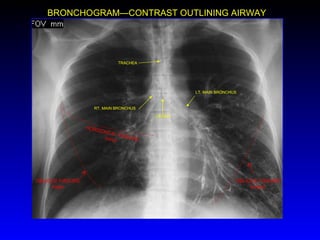

CARINA LT. MAIN BRONCHUS RT. MAIN BRONCHUS TRACHEA OBLIQUE FISSURE (major) OBLIQUE FISSURE major HORIZONTAL FISSURE minor BRONCHOGRAM—CONTRAST OUTLINING AIRWAY

• #11 This exam shows barium contrast outlining the bronchial tree. This is an old exam not done now with CT imaging replacing it. It does demonstrate the anatomy of the hila which superimpose over the pulmonary arteries and veins. This is why anatomy here on the chest X-ray is difficult in this region.